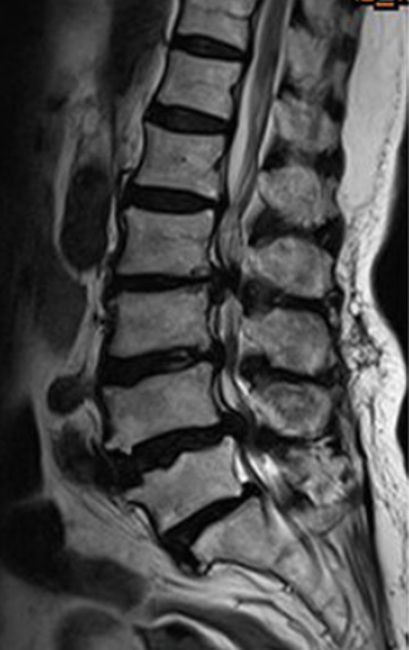

Modic changes are natural changes seen in spine MRI. They show swelling or changes in the bones near the disc and may or may not cause pain.